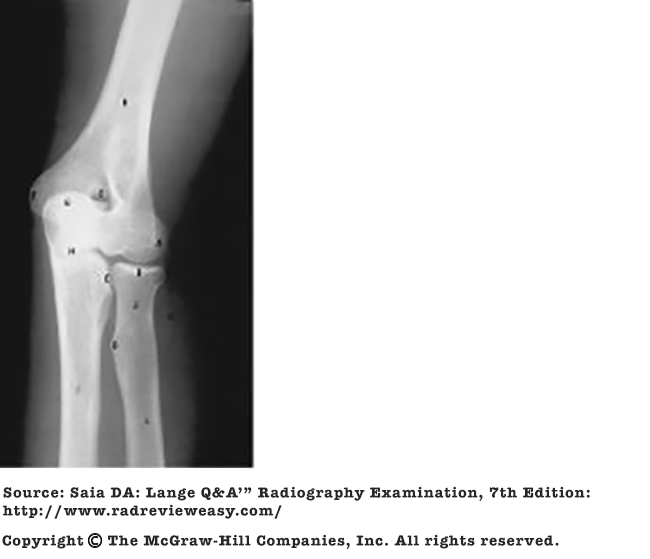

Which of the following statements regarding the radiograph in Figure A is (are) true?

1. The tibial eminences are well visualized.

2. The intercondyloid fossa is demonstrated between the femoral condyles.

3. The femorotibial articulation is well demonstrated.

1 and 3 only